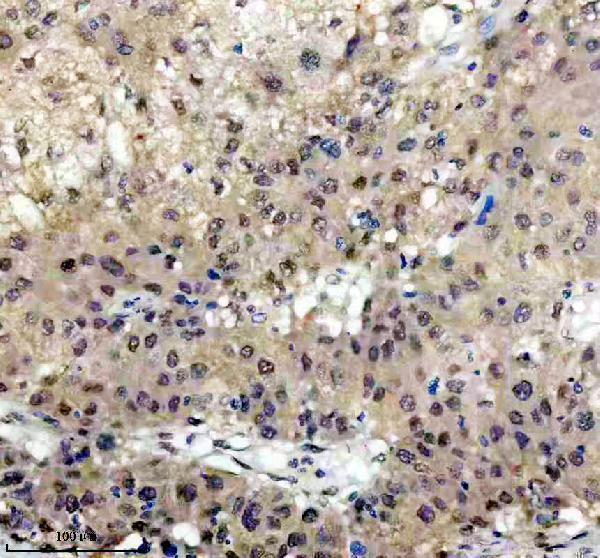

Facts about Insulin gene enhancer protein ISL-1.

Cooperates with the transcription factor POU4F2 to reach maximal levels of expression of RGC target genes and RGC fate specification in the developing retina. Involved in the specification of motor neurons in cooperation with LHX3 and LDB1.

Expressed in subsets of neurons of the adrenal medulla and dorsal root ganglion, inner nuclear and ganglion cell layers in the retina, the pineal and some regions of the brain.